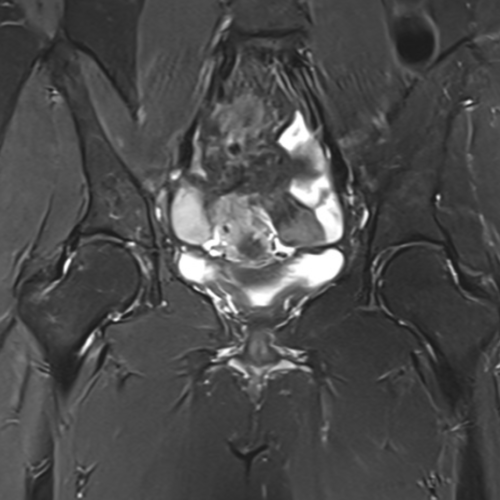

Cet examen est réalisé pour analyser le bassin, les hanches, les tendons fessiers, les articulations sacro-iliaques en cas de douleurs ou fessalgies.

Cette examen permets de diagnostique les tendinites des fessiers, de la lamme latérale, du moyen glutéal, la coxarthrose, les ostéonécroses de hanches, les sacro-iliites rhumatismales des spondyloarthrites.